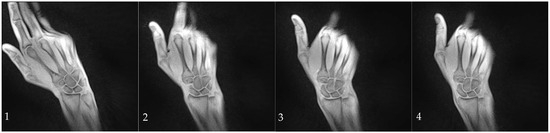

The participants were given commands through headphones to move radially or ulnarly within the previously practiced range of motion at a constant speed. The movement sequence was performed five times with two-minute breaks between each sequence. A subset of participants additionally performed a fist clench maneuver by compressing an elastic ball in a neutral position. During dynamic imaging, a series of 2D images were acquired every 50 milliseconds with an in-plane resolution of 0.75 mm and a slice thickness of 4 mm given a field of view of 192 mm and a matrix of 256 × 256 (Figure 1, Video S1 and S2).

Figure 1. Series of images captured from radial (1) to ulnar deviation (4) during the abduction/adduction maneuver. These images were acquired using a T1-weighted rtMRI sequence with iterative reconstruction, achieving a temporal resolution of 50 ms. Images (14) correspond to frames 156, 207, 226, and 262 out of a total of 300 frames.